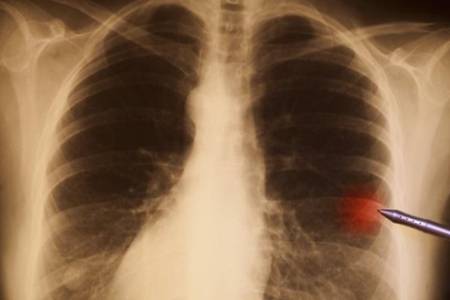

很多人在体验的时候会发现肺部有小结节的情况,肺结节到底是怎么回事?体检发现肺结节该怎么办?其实,肺结节是指肺实质内直径≤3 cm 的类圆形或不规则病灶,影像学表现为密度增高的阴影,多数情况下不用治。接下来,大家就和小编一起来看看吧。

虽然引起肺结节的原因是非常多的,但主要还是炎症性和肿瘤性两大类。炎症性的肺结节,主要是指肺炎、肺结核等肺部发生炎症,经过药物治疗或者自身免疫力的作用下,炎症痊愈但在肺部留下了疤痕或者影子。

肿瘤性的肺结节,主要是指在肺部正常的组织中生长了肿瘤,不过肿瘤里也有良性的肿瘤,比如:血管瘤,错构瘤等,但也有恶性的肿瘤,最常见的就是肺癌。